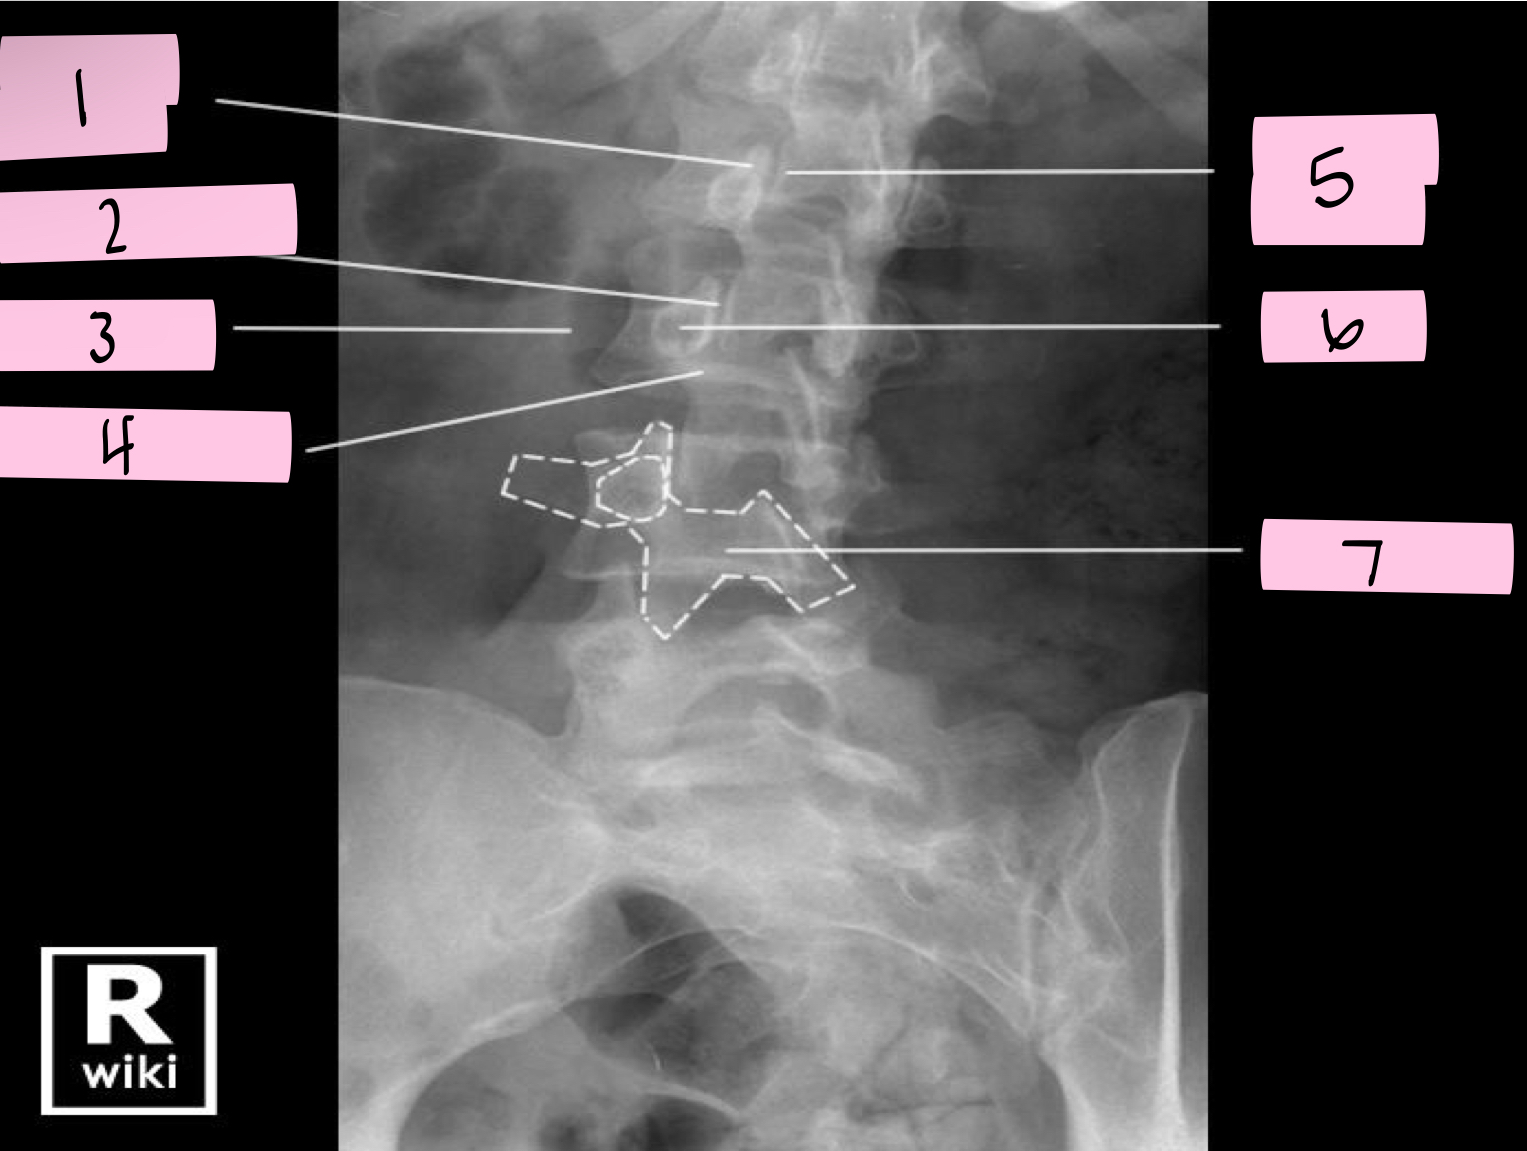

What is 1 pointing to?

Superior articular process

What is 2 pointing to?

Zygapophyseal joint

What is 3 pointing to?

Transverse process

What is 4 pointing to?

Pars interarticularis

What is 5 pointing to?

Inferior articular process

What is 6 pointing to?

Pedicle

What is 7 pointing to?

Scotty dog